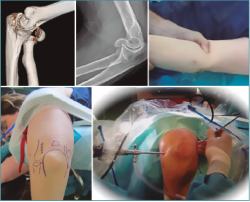

Figura 10. Colocación del paciente, visión articular de la fractura y reducción artroscópica.

Permite un tratamiento eficaz de la fractura sin tener que realizar un extenso abordaje sobre unos tejidos ya de por sí afectados. Igualmente, nos aporta una excelente visión de la fractura así como de su reducción anatómica final (Figura 14). Es preceptivo un adecuado estudio de imagen, así como planificación pre- y postoperatoria.

Figura 14. Colocación en el quirófano. El autor realizando una fractura del codo asistida por artroscopia.